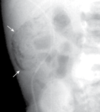

Qual o sinal presente na imagem? Qual seu significado?

Crescente radioluscente. Gás intraperitoneal livre:

Geralmente ocorre por rupturas gastrointestinais, como nos casos de úlcera péptica perfurada, trauma acidental (iatrogenia), cirurgia abdominal (uma das principais causas, mas normalmente gás permanece por pouco tempo, tipo uma semana. Não terá sinais clínicos), diverticulite ou apendicite perfurada, carcinomas. Nesses casos iremos observar ar abaixo do diafragma, visto melhor em ortostatismo e na forma crescente radioluscente.

O melhor exame nesse caso é a TC - para pequenas quantidades de ar intraperitoneal. A radiografia é o exame inicial, sendo utilizado para rastreamento, a alternativa é a realização em decúbito lateral esquerdo.